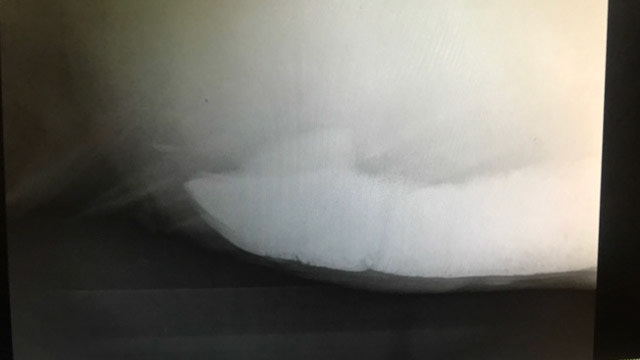

Radiographs showing sand in the colon.